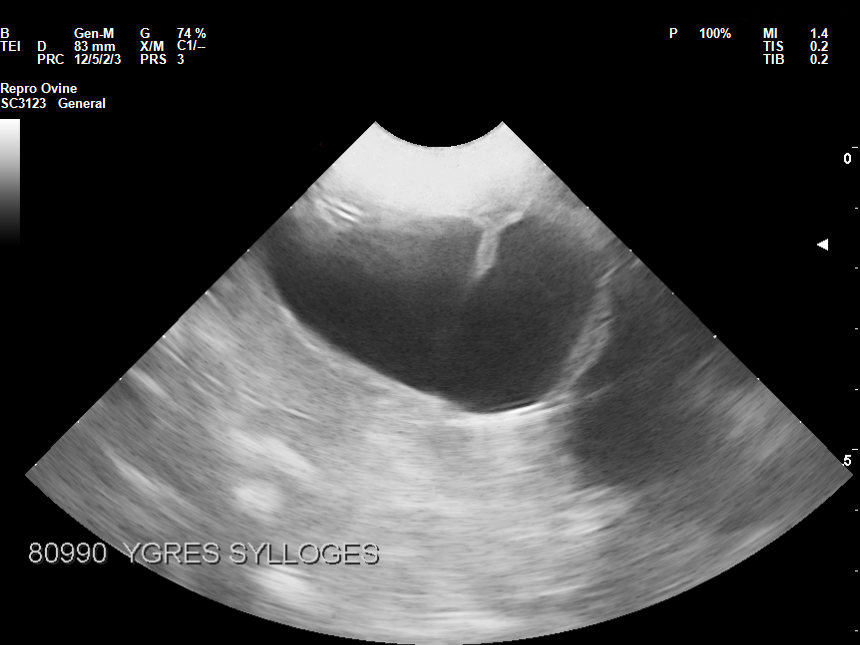

• Διάγνωση εγκυμοσύνης

• Διάγνωση πολυδυμίας